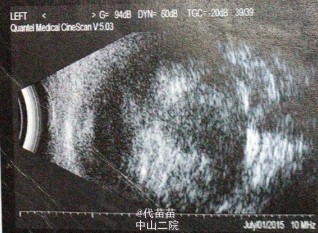

体格检查:专科检查:左眼上睑轻水肿,结膜混合充血明显,瞳孔区白色反光,对光-,角膜轻水肿 辅助检查:1.右眼玻璃体混浊,球壁不光滑声像2.左眼内实性占位性病变声像